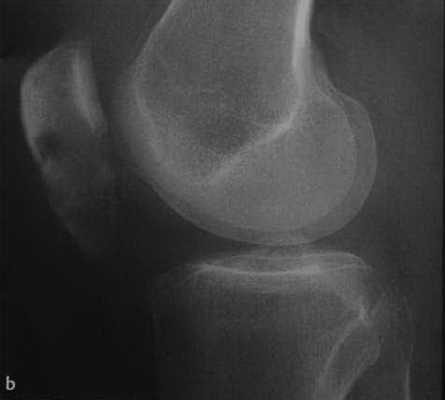

(Справа) При рентгенографии в боковой проекции у этого же пациента определяется поперечный перелом нижней поверхности надколенника с отсутствием смещения. Поперечные переломы иногда возникают вследствие насильного разгибания при сокращении четырехглавой мышцы. (Слева) На рентгенографии в передне-задней проекции определяется продольный перелом надколенника вследствие прямого удара. Острые края перелома позволяют отличить такую травму от надколенника, состоящего из двух частей.

(Справа) МРТ, выполненная после падения на колено, РDВИ, режим подавления сигнала от жира, аксиальный срез: определяется продольный перелом надколенника. Края осколков перелома острые, в них отсутствуют признаки склероза. Отмечается обширный отек костного мозга и разрыв суставного хряща. (Слева) При рентгенографии в передне-задней проекции определяется надколенник, состоящий из двух частей. Края дополнительного центра окостенения гладкие и ровные. Дефект надколенника зачастую крупнее чем вторичный центр, в отличие от перелома, который бы соответствовал по размеру.

а, b Поперечный закрытый перелом надколенника. Рентгенологическое исследование надколенника в прямой (а) и боковой(b) проекциях.

а,b Оскольчатый перелом надколенника со смещением. Рентгенологическое исследование надколенника в боковой (а) и прямой (b) проекциях. Звездчатый перелом с расхождением фрагментов проксимально и дистально.